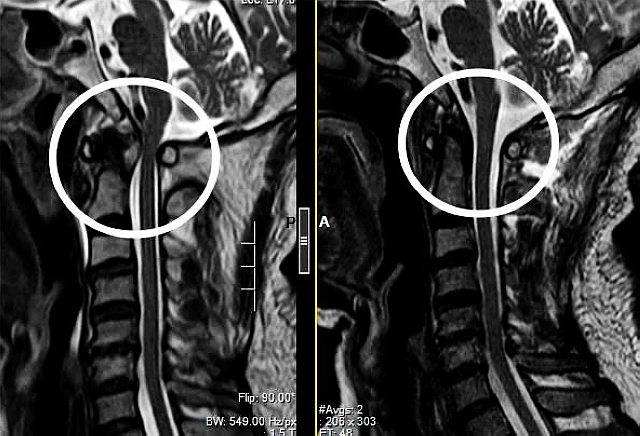

术前术后磁共振

接诊的雷飞教授为周先生做了详细的检查,检查结果显示很糟糕,他向患者解释到:“颈椎三维重建提示枕寰关节脱位,这种情况必须通过手术治疗,恢复枕寰关节的正常解剖位置,否则就是一枚‘定时炸弹',随时都会危及生命。”

雷飞进一步解释说,枕寰关节脱位是一种极其不稳定、极其罕见、生存率极低的颅脊交界区损伤。枕寰关节位于后脑勺,连接着大脑与颈椎,这个区域属于生命中枢,好比是“司令部”,有脑干、脊髓、椎动脉等重要组织结构。一旦发生枕寰脱位,很可能出现下脑干和上颈髓的直接损伤,由于脑干是呼吸和心血管运动中枢,这种直接损伤可导致立即死亡。